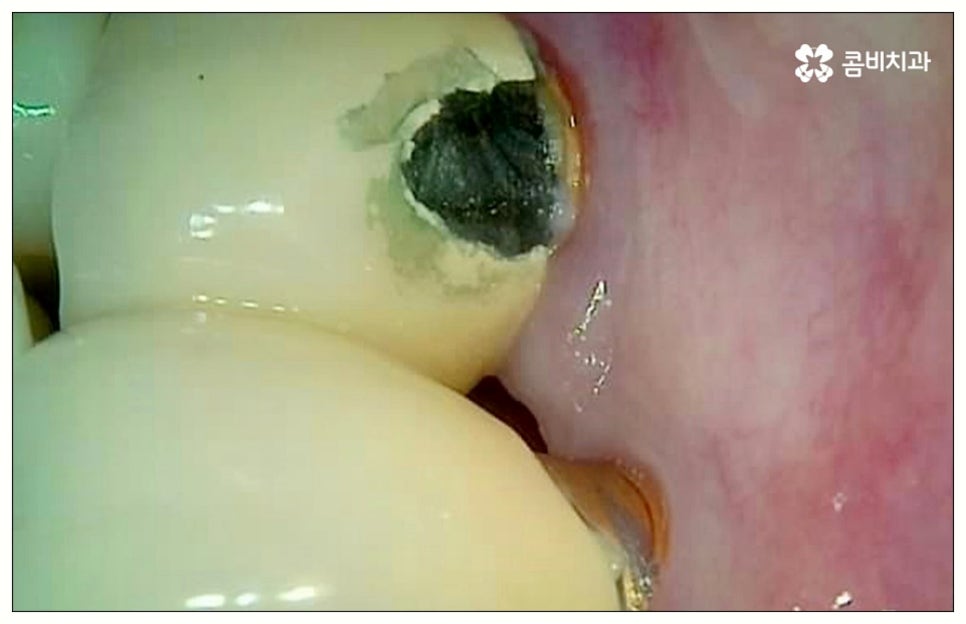

그러나 모든 환자분들이 원데이임플란트 방식을 이용할 수 있는 것은 아니기 때문에 주의하실 필요가 있어요. 말씀드렸던 것처럼 임플란트 수술은 직접 환자의 잇몸뼈에 식립을 진행하는 방식의 치료이기 때문에 잇몸뼈 상태가 양호하지 않은 분들의 경우 발치 후 바로 임플란트를 심는 것이 식립 성공률이나 지속적인 안정성 측면에서 좋지 않을 수 있어요. 특히 잇몸 질환으로 인해 염증이 심한 경우 또는 바탕이 되는 잇몸뼈의 밀도나 높이가 많이 부족한 경우에는 원데이임플란트 방식이 불가능하다고 할 수 있는데요.

이때 만약 무리하게 즉시 식립을 진행하게 되면 임플란트 치아가 제대로 기능하기 어려울 뿐 아니라 주위염 등 부작용을 일으킬 가능성이 높아 주변 잇몸 및 치아에도 좋지 않은 영향을 주게 되며 결국 임플란트가 흔들리거나 빠지면서 재수술이 필요한 상황까지 이를 수 있으므로 필요한 치료부터 선행하는 것이 좋을 거예요. 위에서 예로 든 상황이라면 잇몸 염증을 먼저 꼼꼼하게 치료한 후 또는 뼈이식술을 통해 안정성을 높인 후에 임플란트 식립을 진행하실 필요가 있어요. 이 과정에서 무엇보다 중요한 것은 수술 전 3D CT를 통해 환자의 상태를 정확하고 꼼꼼하게 확인하고, 환자의 연령, 치아를 상실하게 된 원인 및 시기, 식습관 등 관련된 모든 부분을 빠짐없이 검토하여 각자에게 꼭 맞는 계획을 세운 다음 회복 정도를 체크해 가면서 무리하지 않게 진행해 나가는 것이기 때문에 정밀 진단 장비 및 숙련된 의료진이 있는 치과에서 임플란트 치료를 받으시도록 권유드리고 있습니다.